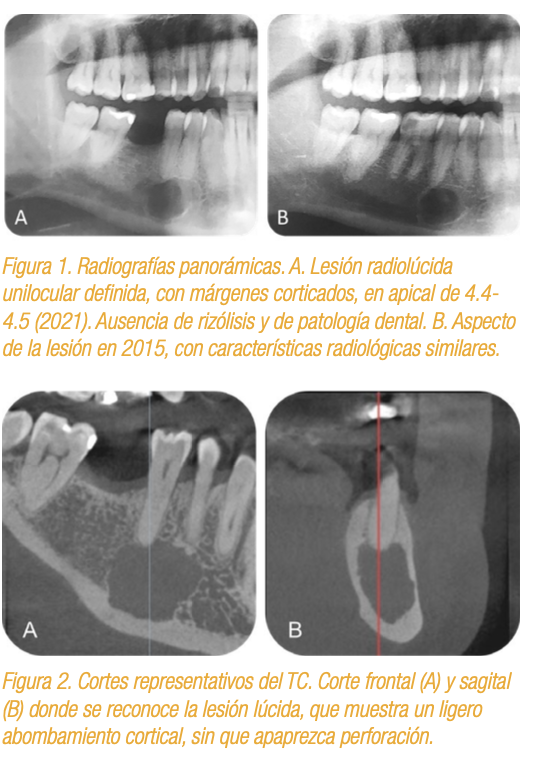

Se trata de un hombre de 58 años, sin antecedentes personales y tóxicos de interés, fue derivado en 2021 por su odontólogo al Centro de Cirugía Oral y Maxilofacial, para la valoración de una lesión mandibular asintomática, con más de 5 años de evolución, situada en el 4o cuadrante, y que últimamente se asocia a episodios de parestesias en la zona. A la exploración clínica no se aprecian alteraciones reseñables y se comprueba que los dientes 4.4 y 4.5 son vitales. El examen radiológico actual muestra una lesión radiolúcida unilocular bien definida con márgenes corticados, situada en la zona apical de los dientes 4.4 y 4.5. No se aprecia afectación radicular ni patología dentaria alguna. También se aporto una RX anterior (2015), previa a la exodoncia del diente 4.6 afecto de una gran lesión de caries. Dada la proximidad de la lesión al nervio dentario inferior, inicialmente se adoptó una actitud de vigilancia (Figura 1).

Con la sospecha clínica de que se trataba de una patología quística de origen odontogénico no inflamatoria, tipo queratoquiste odontogénico, se decide realizar una tomografía computariza- da de la zona (Figura 2), y realizar la escisión quirúrgica de la lesión bajo anestesia local. La muestra obtenida se envió para estudio histopatológico al Servicio Diagnóstico Patología Oral y Maxilofacial (SDPOMF).